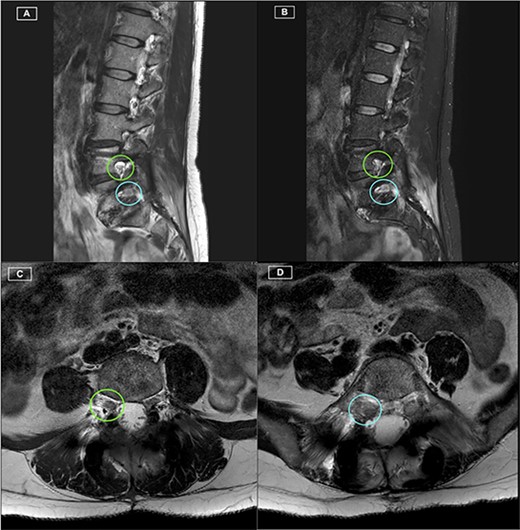

This 45-year-old female presented with low back pain and right-sided L5 radiculopathy involving pain and sensory symptoms extending into the leg. Her symptoms began following an acute event involving a bend, twist and lift injury. She trialled conservative measures, including analgesia, physiotherapy and perineural injections, over a period of 6 months, with persistent symptoms. Imaging revealed bilateral L5 pars defects and a Grade 1 spondylolisthesis resulting in foraminal stenosis with bilateral compression of the exiting right L5 nerve roots. In addition, degenerative disc disease was present at both L4/5 and L5/S1 with contact of the right L5 nerve root in both the right L4/5 lateral recess as well as within the right L5/S1 foramen (Fig. 1). A single photon emission CT bone scan was additionally performed, demonstrating significant uptake in the L4/5 and L5/S1 facet joints. Based on these findings, L4/5 and L5/S1 PLIF were recommended. The patient proceeded to surgery with CFR-PEEK pedicle screws (CarboFix, TelAviv, Israel) and PEEK interbody cages (Evolution Spine, Sydney, Australia) inserted at both levels. Operative time was 3.5 hours, with 240 ml of blood loss and no intraoperative complications.

Preoperative MRI lumbar spine (mid- and para-sagittal slices of T2 weighted sequence) demonstrating posterior bulging of the L4/5 and L5/S1 discs in conjunction with a Grade 1 spondylolisthesis of L5 on S1 resulting in significant right-sided foraminal stenosis at L5/S1 (indicated by yellow arrow).

The patient recovered well, with resolution of her lower limb radiculopathy. Ongoing low back pain was managed by a multidisciplinary pain team. At 6 months post-operative, the patient experienced some recurrence of right leg pain. CT revealed excellent hardware position with no pseudarthrosis. MRI demonstrated adequate decompression of the descending and exiting L5 nerve roots, with minor perineural thickening within the right L5/S1 foramen. This patient was managed conservatively for her pain, given the lack of radiological pathology identified on CT and MRI. Figures 1–3 highlight the low artefact presence on both post-operative MRI and CT, allowing for optimal assessment of bony and neurological structures.

Postoperative MRI Lumbar spine. (A) Right-sided parasagittal slice of T2 Sequence MRI. Right L4/5 foramen (superior) and Right L5/S1 foramen (inferior) have been highlighted, with excellent definition of the Right L4 and L5 nerve roots. (B) Right-sided parasagittal slice of Short Tau Inversion Recovery (STIR) Sequence MRI. Exiting L5 nerve root is well visualised, with evident perineural thickening. (C) Axial slice of T2 Sequence MRI at the level of the L4/5 Foramen. The Right L4 nerve root is identified with excellent visualisation. (D) Axial slice of T2 Sequence MRI at the level of the L5/S1 Foramen. The Right L5 nerve root is identified with excellent visualisation.